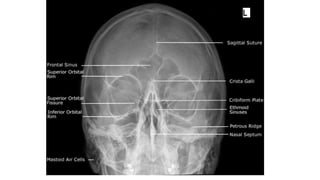

Caldwell view [occipito frontal with 15 deg caudad]

• This projection is used to demonstrate the frontal

and ethmoid sinuses.

• Positioning of patient :

• Patient is seated facing the erect bucky

• Neck is flexed to bring nose and forehead in contact

with the bucky.

• orbito meatal line perpendicular to the bucky,

• Central ray :

• Ray is directed perpendicular to the bucky along

the median sagittal plane.

• The tube is rotated 15 deg caudal to the orbito

meatal baseline

• centered 1/2 inch below the external occipital

protruberance

Caldwell view [occipitofrontal with 15 deg caudad] • This projection is used to demonstrate the frontal and ethmoid sinuses. • Positioning of patient : • Patient is seated facing the erect bucky • Neck is flexed to bring nose and forehead in contact with the bucky. • orbito meatal line perpendicular to the bucky,

• 20.

• Central ray: • Ray is directed perpendicular to the bucky along the median sagittal plane. • The tube is rotated 15 deg caudal to the orbito meatal baseline • centered 1/2 inch below the external occipital protruberance